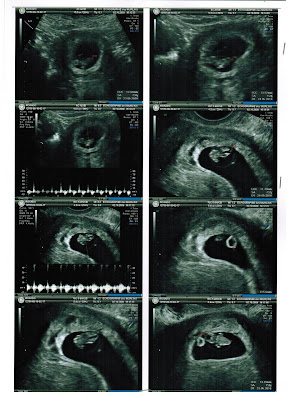

... ou melhor, 11 semanas e 5 dias e 53mm de gente a crescer dentro de mim! Tem uns pézinhos minimos que mal se vêem, o coração bate a 162/min, o estômago é visivel no local certo, o cérebro está formado e tem os dois hemisférios distintos e definidos... e mais coisas que só vendo.... eheheh

E não, infelizmente ainda não conseguimos saber se é munino ou munina... agora temos de esperar (todos) até dia 6 de Janeiro...

Vejam bem o que o/a malandreco/a anda a fazer... não admira que eu ande sempre cansada... lol

5ª feira de manhã é a primeira grande ecografia... :)

A ecografia de hoje mostrou que estamos a 7 semanas e 5 dias de gravidez e o baby tem 14mm. O coração bate a uma velocidade vertiginosa o que prova que está tudo a correr às mil maravilhas!